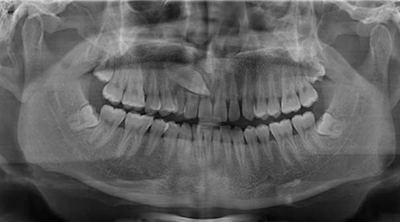

牙片

牙片是指牙齒的X線片,也稱口內(nèi)標(biāo)準(zhǔn)片。一張牙片可以顯示3-4個(gè)牙齒,牙齒在牙片上顯示出白色阻射影像。牙片是口腔科應(yīng)用最廣的檢查手段,也是最常用的,因?yàn)樗谘赖闹委熐?、治療中和治療后都有助于診斷和治療。當(dāng)然,牙片電離輻射對(duì)人體也具有一定的危害。

其面積為3×4平方厘米。一張牙片可以顯示3-4個(gè)牙齒。牙齒在牙片上顯示出白色阻射影像。其中牙釉質(zhì)阻射最強(qiáng),牙本質(zhì)和牙骨質(zhì)阻射低于牙釉質(zhì)。牙髓腔呈黑色透明影像,根管口至根尖孔呈逐漸變細(xì)的影像。